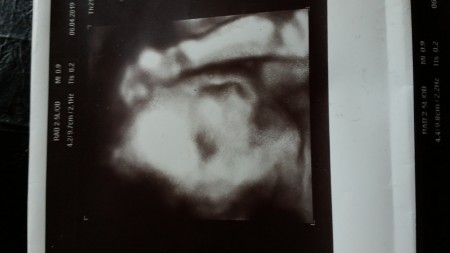

bu da benim kızım ❤️ evet saçları oluyor doktor da öyle demişti.

Oy masallah baya belli. Ama biz renkliyken boyle yoktu siyah beyaz cikti verince sanki sac gibi duruyo kararti. Bilemedim :)

Sadece yüzünü renkli gösterdi diğer organları hep siyah beyazdı.  Ayrıntılı ultroson da oluyormuş sadece renkli zaten canım.

Yok cnm ayrintili da gordum yuzumuzu 20 haftalikken. Ama bunu özelde baktirmistik abimiz merak ediyordu. Orda ekranda renkliydi ciktiyi siyah beyaz verdi doktor. Ayrintili daki renkli halinde senin bebisinki gibi saca benzer bisi yoktu :)